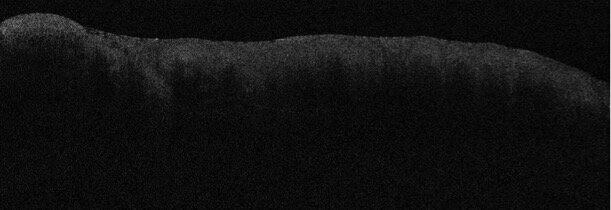

Ma oltre alla fotografia digitale, l’Odontostomatologia può da poco fruire della tecnologia “Optical Coherence Tomography” − OCT per lo studio in vivo e non invasivo degli strati superficiali delle mucose orali (Figg. 3a- 3c). Tecnologia molto conosciuta in ambito oculistico e dermatologico, l’OCT permette di ottenere immagini a sezione trasversale dei tessuti biologici che assomigliano a quelle ottenute con gli ultrasuoni. Entrambe le metodiche sfruttano un segnale retrodiffuso, riflesso dai differenti strati del tessuto, per ricostruire un’immagine strutturale. La differenza è che l’OCT sfrutta un fascio di luce e non di onde sonore.

L’alta risoluzione spaziale dell’OCT permette, quindi, di effettuare anche per la Medicina orale quella che viene chiamata “biopsia ottica” fornendo informazioni diagnostiche in tempo reale sul sito esaminato. Le immagini sono ottenute in vivo con l’uso di una sonda per OCT a fibre ottiche flessibili.

L’OCT possiede un ampio range di potenziali applicazioni nella diagnosi di patologie a carico di svariate strutture del corpo umano come ad esempio l’occhio, la pelle, il tratto gastrointestinale, respiratorio, genito-urinario e il cavo orale. Al momento, presso il Settore di Medicina Orale (G. Campisi, G. Capocasale, V. Panzarella), si stanno studiando e sviluppando le applicazioni su cancro orale e lesioni potenzialmente maligne e su quelle desquamative e vescicolo-bollose, grazie all’utilizzo di un moderno dispositivo di ATeN (Advanced Technologies Network) Center dell’Università di Palermo. Alla fine dell’indagine, si potranno combinare i quadri clinici, le foto digitali e le immagini OCT per decidere i siti della mucosa orale più utili ai fini della biopsia e della diagnosi isto-morfologica.

Fig. 3c - Immagine Optical Coherence Tomography (OCT) di Carcinoma orale in paziente donna di 86 anni.